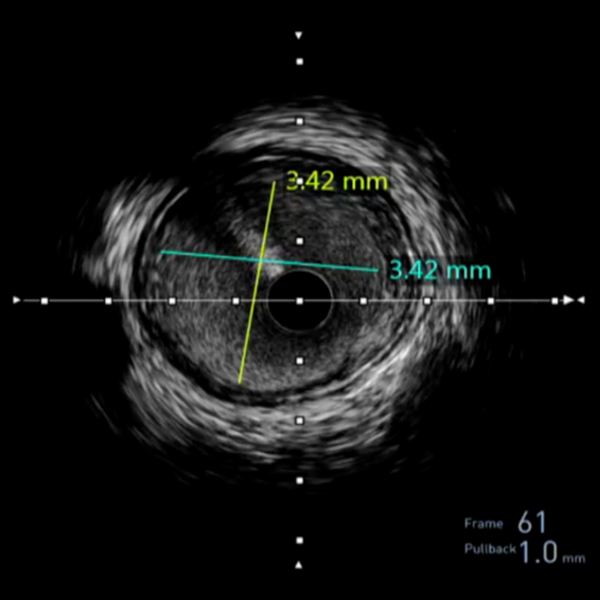

Measurements

• Master accurate measurements with IVUS technology.

• Learn how to acquire and analyze essential data for informed clinical decisions.

Comprehensive vessel view with precise measurements